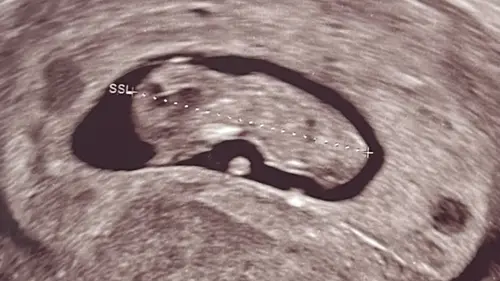

Ons hummeltje wilde zich niet goed laten zien, dit was maar 1 seconden maar gelukkig gemeten en we zijn weer 5 dagen vooruit gezet. 30/7 uitgerekend ✨